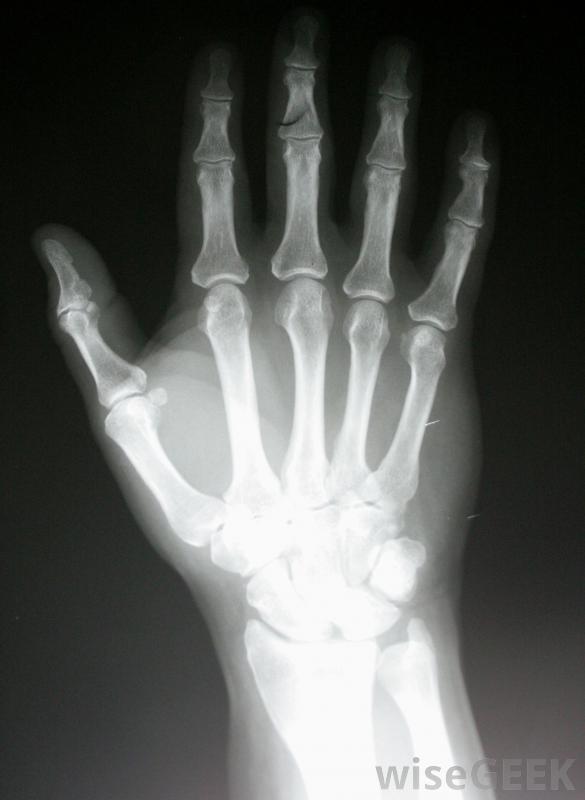

X光片可能会显示出骨炎症和不寻常的生长模式。SAPHO综合征的病因尚不清楚。怀疑至少部分是一种自身免疫性疾病,即人体自身免疫系统错误地攻击健康的骨骼、皮肤,以及关节组织。医生不确定这种疾病是否是遗传的,因为它非常罕见,而且大多数病例似乎不是家族遗传的。没有传染源或特定的环境毒素与SAPHO综合征有关。任何年龄都可能出现症状,但通常见于中老年人

局部使用皮质类固醇软膏有助于缓解与SAPHO综合征相关的疼痛和肿胀。专家小组可能参与确定诊断皮肤状况通常可以通过体格检查来确定,而诊断性的影像学扫描如x光片可以显示出骨炎、异常的生长模式和关节受累。血样可以被分析以排除其他潜在的病因,如感染和更为人所知的自身免疫性疾病

检查X光片可以帮助医生诊断SAPHO